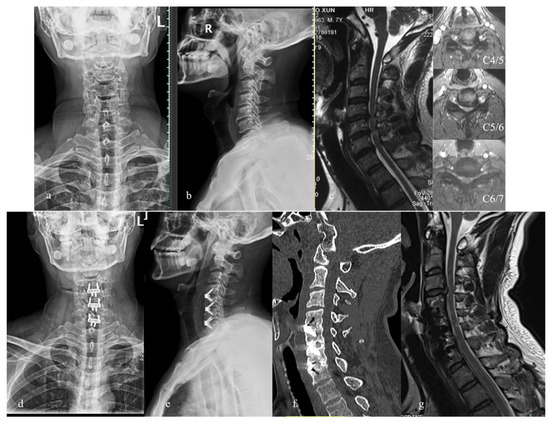

2. Materials and Methods

3. Results